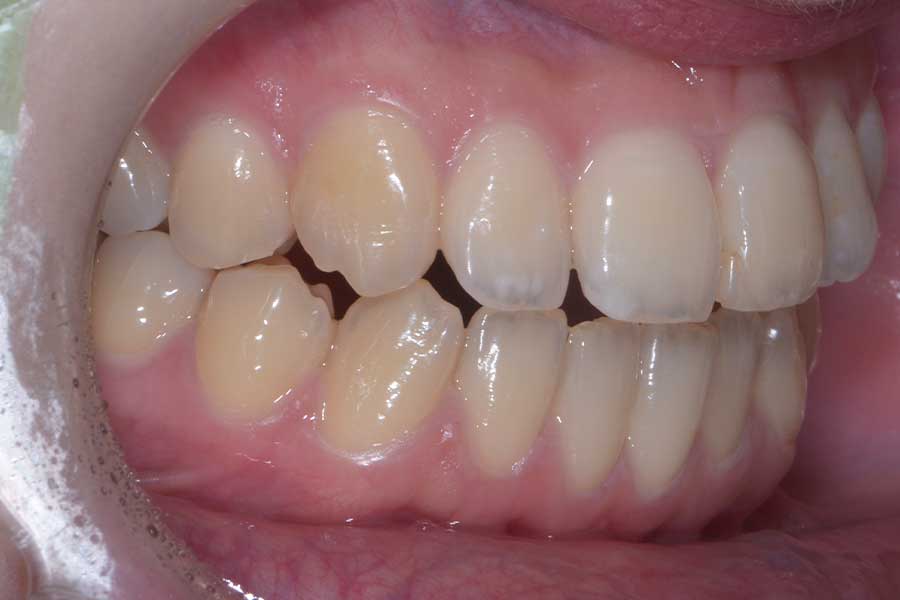

【20代女性】前歯で咬み切れるようになりたい

治療前

主訴 前歯で咬み切れるようになりたい

治療内容 ハーフリンガル矯正(上顎裏側・下顎表側矯正)